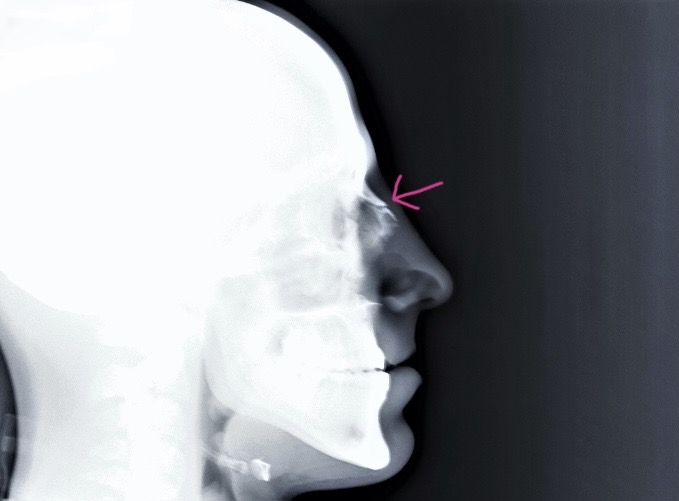

Cómo se planifica la rinoplastia reconstructiva

Cada caso postraumático es único. Por ello, se realiza:

- Estudio clínico completo

- Evaluación respiratoria

- Análisis estructural nasal

- Valoración fotográfica

- Plan quirúrgico personalizado

En muchos casos, se requiere un enfoque estructurado, reforzando cartílagos debilitados o recolocando huesos con precisión milimétrica.